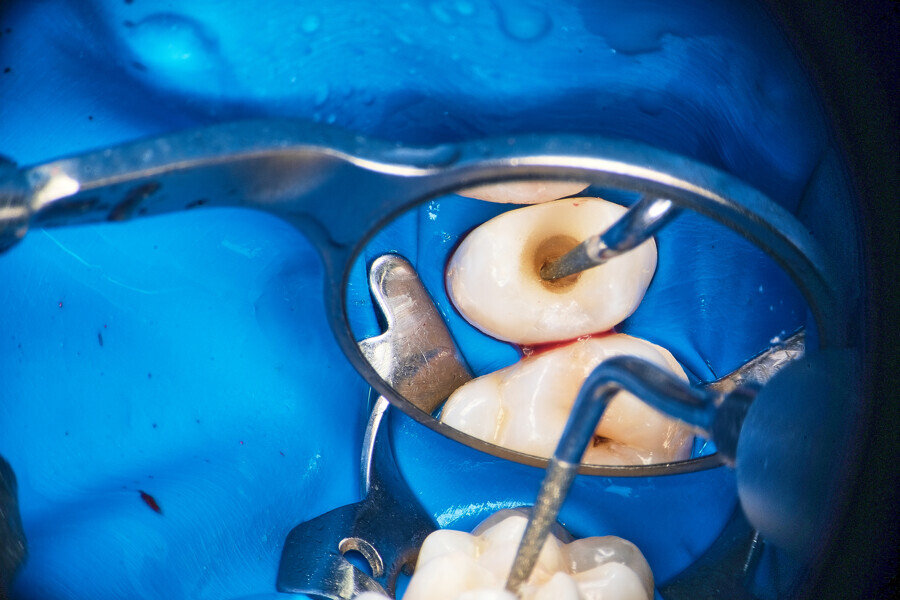

Fig. 1.

The piston technique is simple and predictable. Once the final preparation and irrigation protocol has been performed, owing to the specific properties of CSBSs, the canal should not be overdried. A small amount of moisture should remain in the canal space as the catalyst for the setting reaction of the sealer. With the application needle introduced to the maximum level of the insertion, gently eject the material from the syringe directly into the canal space. To avoid extrusion, try not to block the needle in the canal. After seeing the material in the canal space, remove the needle and use a hot gutta-percha extruder to create a plug in the coronal part. Next, push the coronal part of the gutta-percha with the cold plugger towards the apical zone. Do not push more than 1–2 mm (Fig. 1).